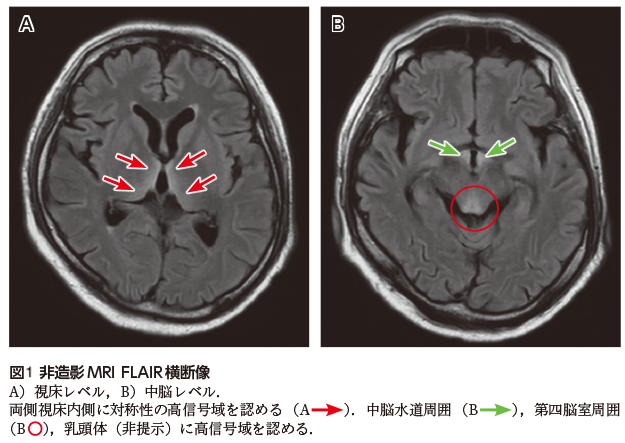

• A1:FLAIR像で視床内側(図1A),中脳水道周囲(図1B),第四脳室(図1B),乳頭体の高信号〔拡散強調像でも同部位は淡い高信号を示す(図2の連続画像を参照)〕.

画像所見では,前述の障害部位に一致する第三脳室(視床内側),中脳水道周囲,第四脳室底,乳頭体にT2強調像やFLAIR像で対称性の高信号を認める1).造影増強効果を呈することもあるが,特に乳頭体でみられることが多い1).その他の病変部位として,稀に小脳や脳神経核,赤核,脳梁,大脳皮質にも病変が認められることがある2).予後との関連では,中脳水道のみが侵された症例では予後良好で,視床内側の高信号域や乳頭体の造影効果を認めた場合には精神障害が残り,Korsakoff症候群を呈することもある1)